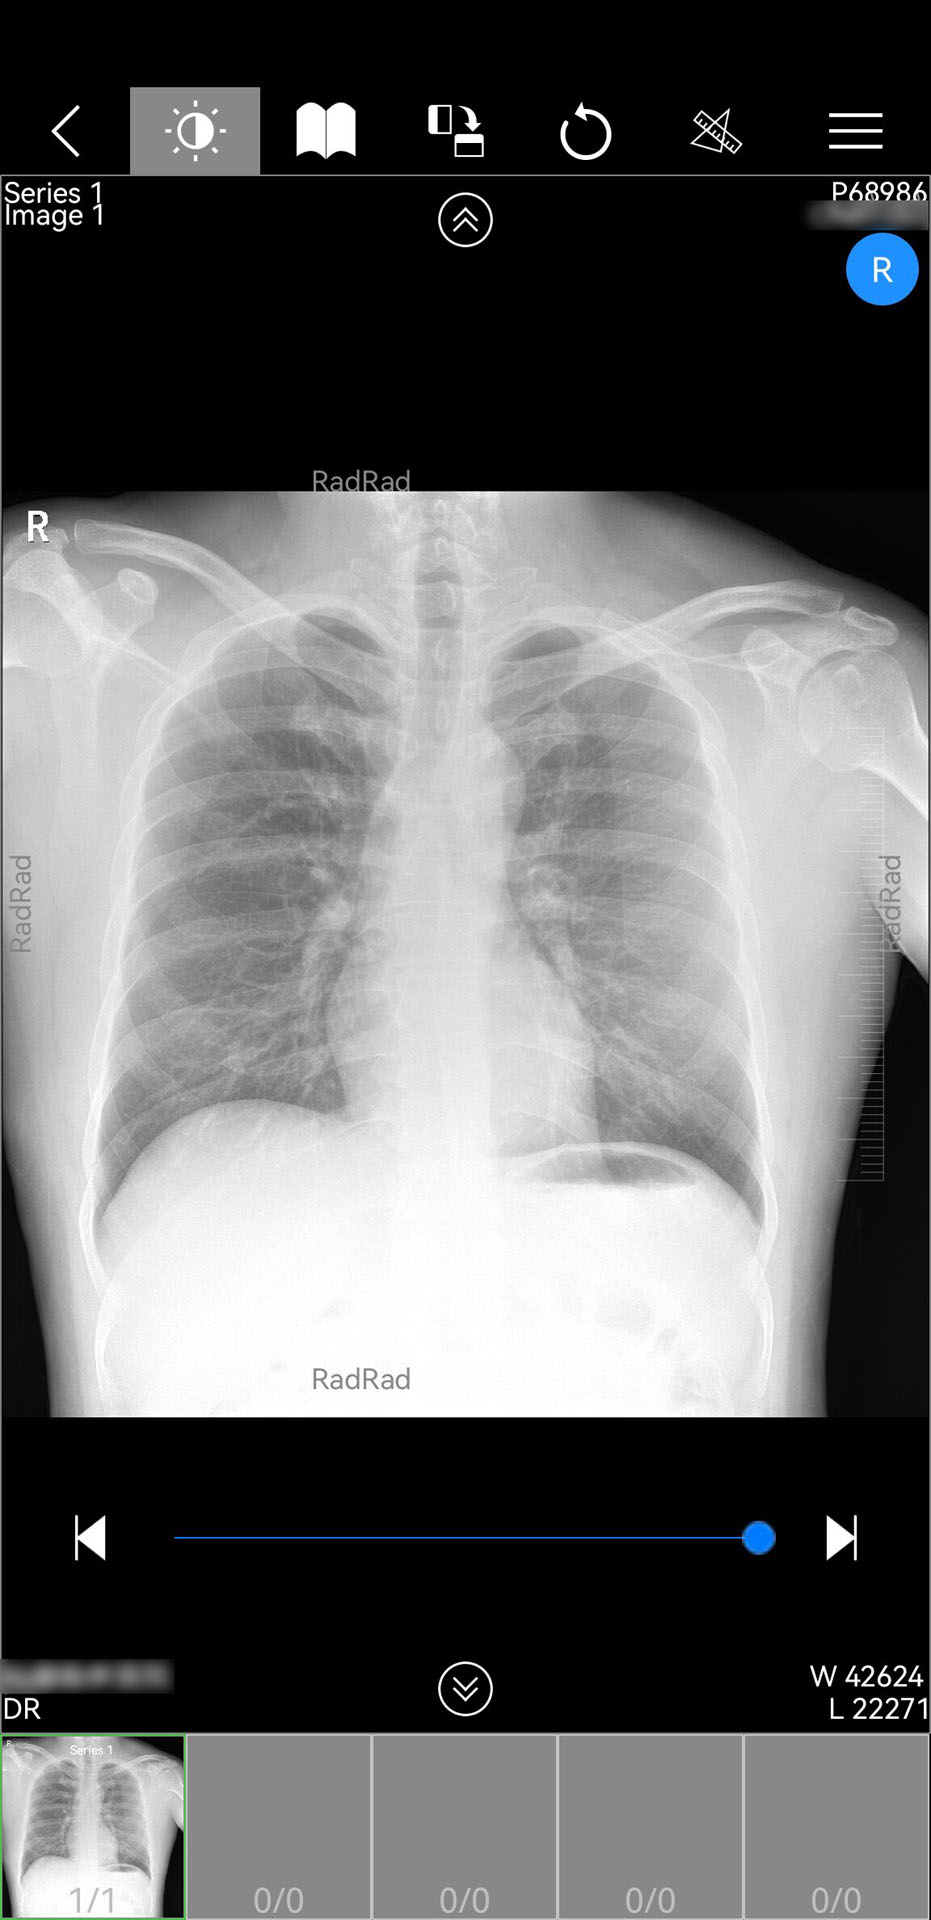

微影医生电脑版是一款医疗应用,提供病人信息获取、检查报告查看和影像查看等功能,支持医生之间信息共享和会诊,界面友好,操作简便,让医生随时随地高效完成诊断工作,并易于维护和提供可靠的性能。

微影医生APP应用软件构建在业界流行的Android平台上,借助移动设备的计算、存储和联网能力,基于云服务器基础上,实现了方便快捷获取病人信息,查看病人检查报告、PDF文档、电子胶片和检查影像功能,同时可以把该病人的检查信息分享给别的医生查看。

微影医生APP软件,连接对应云服务器,方便医生根据影像和报告进行诊断,同时,医生可以把病人检查信息以短信方式分享给指定医生查看,可以随时随地进行诊断或会诊。